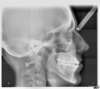

Béance traitée sans chirurgie par plaques d'ingression

Téléradio